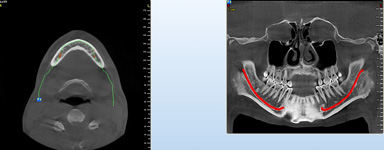

Pro následné plánování využíváme počítačové programy NewTom Implant Planning a coDiagnostiX, které slouží na plánování vhodných pozic pro zavedení implantátů, operačních šablon, kostních bloků, pozdějších protetických náhrad, ...

- operace pomocí OP šablon. Ve speciálním programu coDiagnostiX se využívají data z CB CT scanu - tedy údaje o množství a kvalitě kosti, dále data získaná ze scanu modelu čelistí s modelem plánované protetické náhrady (korunky, můstku…)

- tedy údaje tloušťce sliznice, pozice a tvaru náhrady.

Tím máme všechny potřebné údaje pro plánování pozic implantátů, jejich potřebné délce a průměru. Abychom mohli implantáty zavést do naplánovaných pozic v ústech pacienta, umožňuje tento program vymodelovat speciální operační šablonu, která je zhotovena 3D tiskárnou. Pomocí této šablony, která se umístí do úst pacienta, pak probíhá vlastní operace

Jedná se o plánovací program, který využívá dat získaných při vyšetření pomocí přístroje New Tom. Tento program umožňuje tříprostorovou počítačovou simulaci při plánování pozic implantátů.

Lékař si vytvoří všechny typy zobrazení potřebných pro naplánování – tedy 2D snímky (panoramatický), příčné řezy i 3D model.

Vidí zde i důležité anatomické útvary – čelistní dutinu, průběh nervu atd. Po proměření množství kosti – šířky i výšky vybere z databáze vhodný typ implantátu a umístí ho do požadované lokality.

Ihned vidí jeho pozici ve všech 3 rovinách a na všech snímcích i 3D modelu. Může upravovat podle potřeby jeho pozici, sklon atd.

Jedná se o externí plánovací program, spojený se zubní laboratoří a frézovacím centrem, který využívá dat získaných z 3D rentgenu čelisti, otisku zubů a dásně (scanu zubů a dásně) a finálního návrhu protetické náhrady.

Tento program umožňuje tříprostorovou počítačovou simulaci při plánování pozic implantátů. Součástí programu je i databáze, ve které mohou být uloženy všechny typy implantátů od všech výrobců, včetně jejich délek, průměrů i tvarů.

Lékař si vytvoří všechny typy zobrazení potřebných pro naplánování – tedy 2D snímky (panoramatický), příčné řezy i 3D model.

Vidí zde i důležité anatomické útvary – čelistní dutinu, průběh nervu atd. Po proměření množství kosti – šířky i výšky vybere z databáze vhodný typ implantátu a umístí ho do požadované lokality. Ihned vidí jeho pozici ve všech 3 rovinách a na

všech snímcích i 3D modelu. Může upravovat podle potřeby jeho pozici, sklon atd.